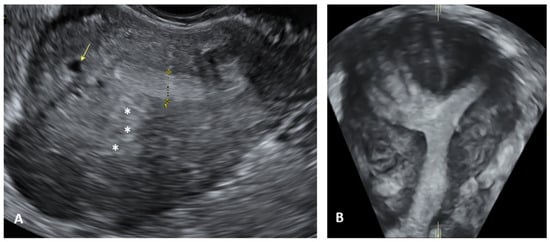

- Deep infiltrating endometriosis (DIE), defined as a lesion infiltrating the peritoneum and involving the retroperitoneal space or the walls of pelvic organs, larger than 5 mm.

- Goncalves, M.O.; Neto, J.S.; Andres, M.P.; Siufi, D.; de Mattos, L.A.; Abrao, M.S. Systematic evaluation of endometriosis by transvaginal ultrasound can accurately replace diagnostic laparoscopy, mainly for deep and ovarian endometriosis. Hum. Reprod. 2021, 36, 1492–1500. [Google Scholar] [CrossRef] [PubMed]

- Condous, G.; Gerges, B.; Thomassin-Naggara, I.; Becker, C.; Tomassetti, C.; Krentel, H.; van Herendael, B.J.; Malzoni, M.; Abrao, M.S.; Saridogan, E.; et al. Non-invasive imaging techniques for diagnosis of pelvic deep endometriosis and endometriosis classification systems: An International Consensus Statement. Ultrasound Obstet. Gynecol. 2024, 64, 129–144. [Google Scholar] [CrossRef]

- Guerriero, S.; Condous, G.; van den Bosch, T.; Valentin, L.; Leone, F.P.; Van Schoubroeck, D.; Exacoustos, C.; Installé, A.J.; Martins, W.P.; Abrao, M.S.; et al. Systematic approach to sonographic evaluation of the pelvis in women with suspected endometriosis, including terms, definitions and measurements: A consensus opinion from the International Deep Endo-metriosis Analysis (IDEA) group. Ultrasound Obstet. Gynecol. 2016, 48, 318–332. [Google Scholar] [CrossRef]

- Van den Bosch, T.; Dueholm, M.; Leone, F.P.; Valentin, L.; Rasmussen, C.K.; Votino, A.; Van Schoubroeck, D.; Landolfo, C.; Installé, A.J.; Guerriero, S. Terms, definitions and measurements to describe sonographic features of my-ometrium and uterine masses: A consensus opinion from the Morphological Uterus Sonographic Assessment (MUSA) group. Ul-trasound Obstet. Gynecol. 2015, 46, 284–298. [Google Scholar] [CrossRef] [PubMed]

- Harmsen, M.J.; Bosch, T.V.D.; de Leeuw, R.A.; Dueholm, M.; Exacoustos, C.; Valentin, L.; Hehenkamp, W.J.K.; Groenman, F.; De Bruyn, C.; Rasmussen, C.; et al. Consensus on revised definitions of Morphological Uterus Sonographic Assessment (MUSA) features of adenomyosis: Results of modified Delphi procedure. Ultrasound Obstet. Gynecol. 2022, 60, 118–131. [Google Scholar] [CrossRef]

- Exacoustos, C.; Lazzeri, L.; Martire, F.G.; Russo, C.; Martone, S.; Centini, G.; Piccione, E.; Zupi, E. Ultrasound Findings of Adenomyosis in Adolescents: Type and Grade of the Disease. J. Minim. Invasive Gynecol. 2021, 29, 291–299.e1. [Google Scholar] [CrossRef] [PubMed]